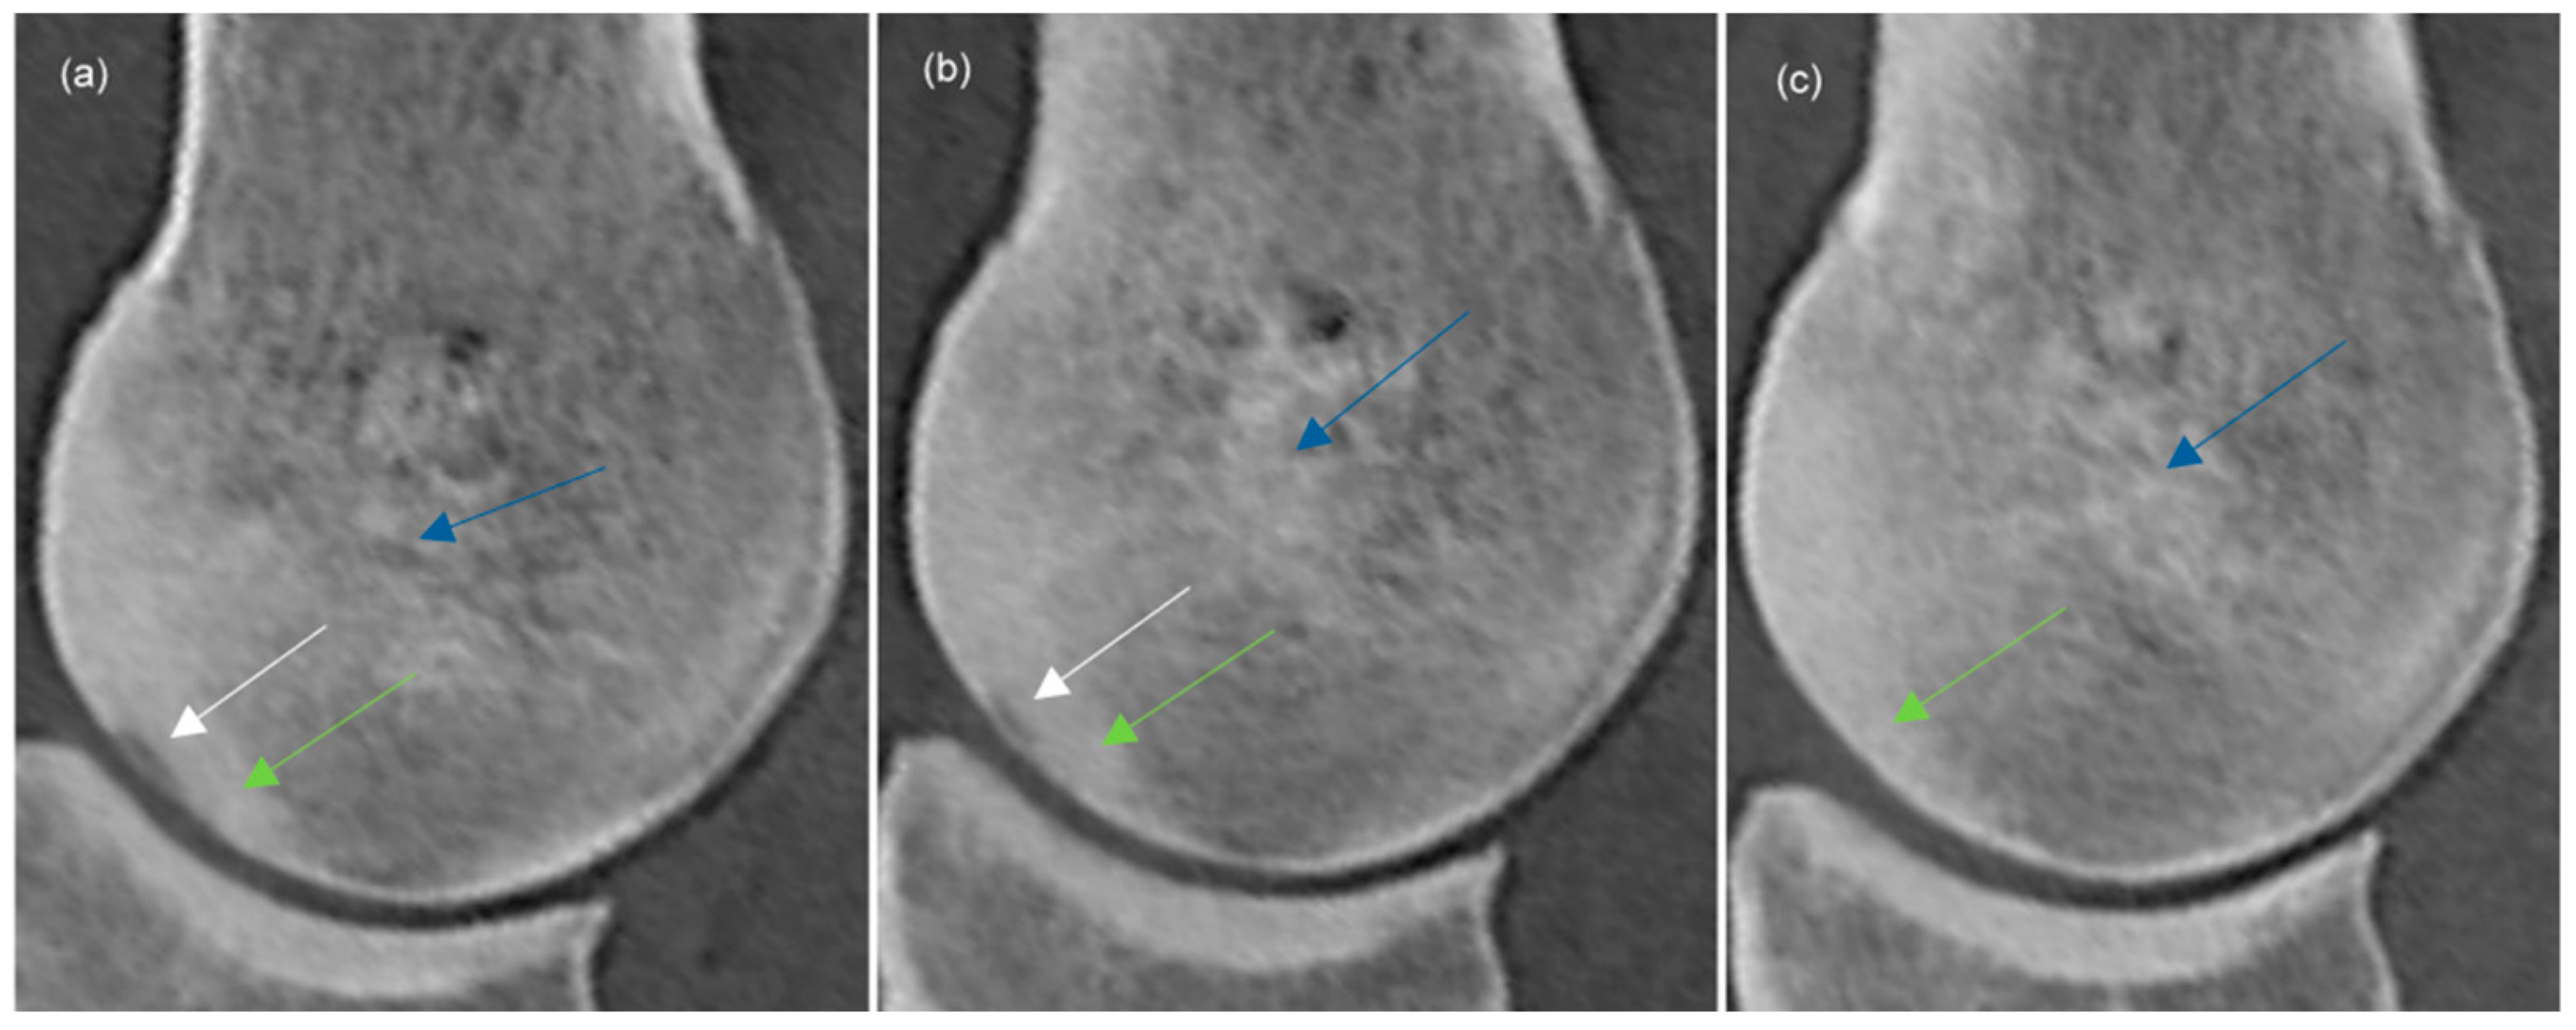

| Shape | ||||

| Proximodistally elongated | 12 | 6 | 5 | |

| Extending towards trabecular bone | 16 | 10 | 5 | |

| Depression | 1 | 1 | 1 | |

| Indentation | 2 | 1 | 1 | |

| Subtle | 2 | 4 | 2 | |